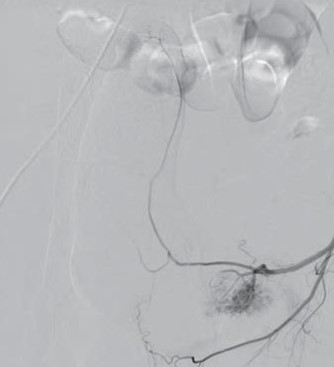

Paciente de 27 anos com quadro de priapismo persistente foi submetido ao exame exposto a seguir para avaliação do quadro:

Com base nos dados apresentados, pode-se afirmar que